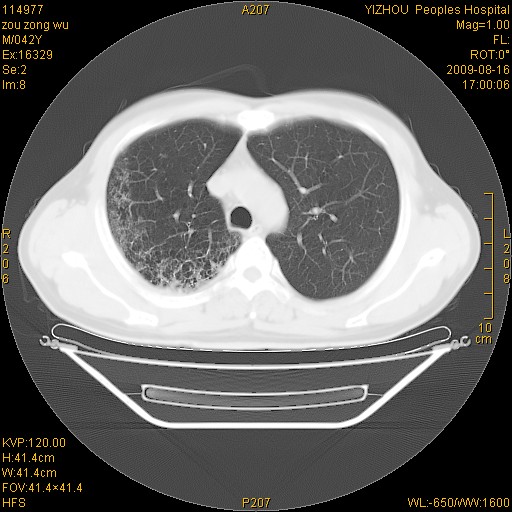

以下是引用zjzjr在2009-8-17 10:42:00的发言:[br]右侧间质性肺炎伴纤维化,右肺下叶肺囊肿伴感染(不除外外伤后引起),右肺野及胸壁软组织\\肝内见多发斑点状,中枪了吧.右侧胸膜肥厚\\粘连.